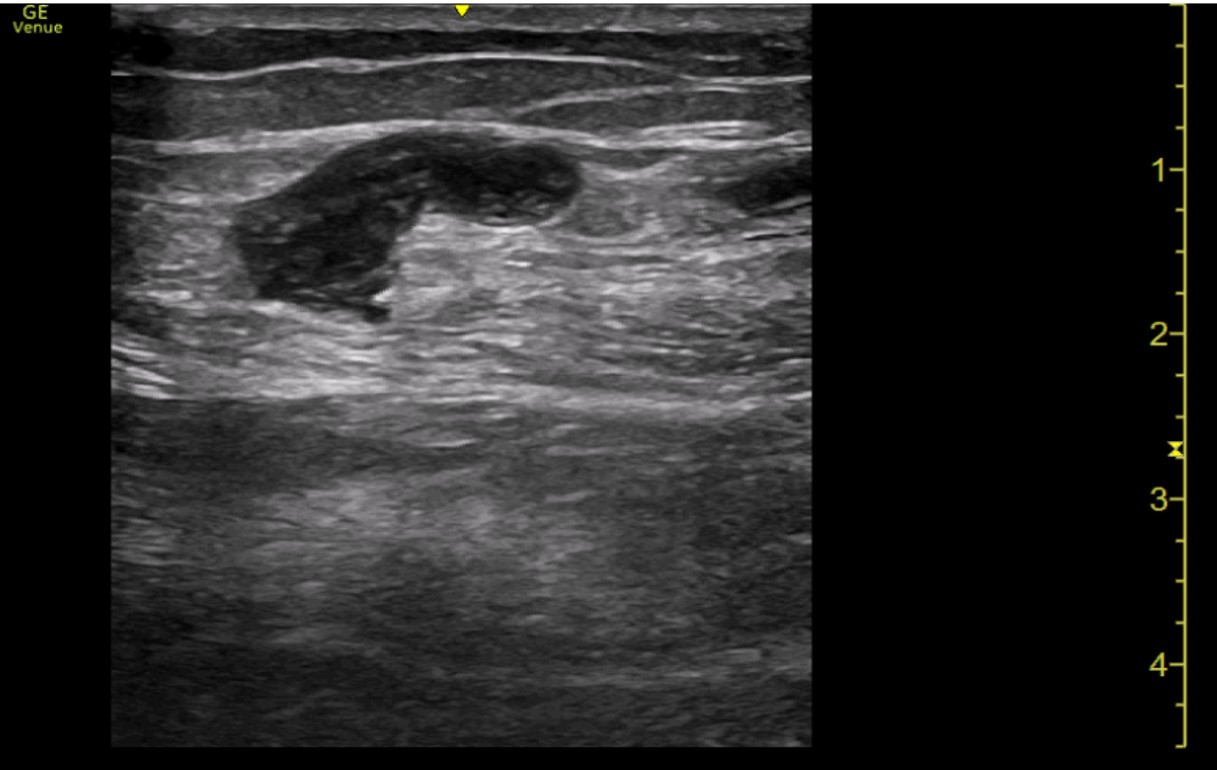

Ecografía a pie de cama: Con sonda lineal, se comienza visualizando vena femoral profunda, la unión de vena safena mayor y la vena poplítea, todas ambas con buena compresión. Por último, se visualiza región dolorosa del paciente, donde se observa vena superficial con contenido hiperecogénico en su interior y ausencia de cambios con la compresión. Se delimita dicha región con longitud inferior a 5 cm y a más de 5 cm de unión safeno-poplítea.